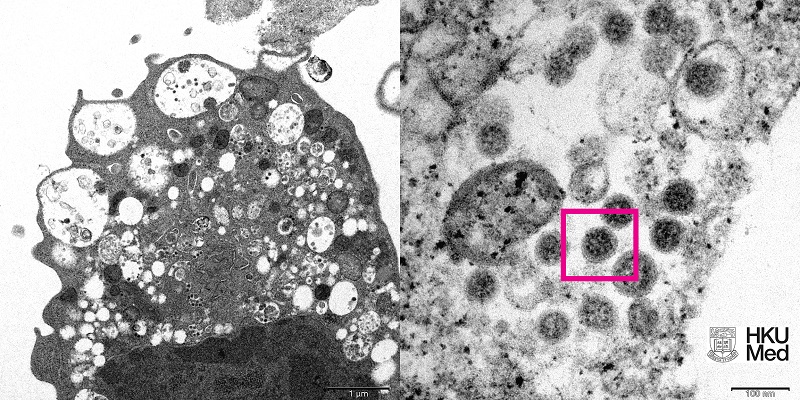

Foto varian Omicron yang diambil menggunakan mikroskop elektron oleh para ilmuwan di Universitas Hong Kong/Ist

rmol news logo Universitas Hong Kong telah merilis foto asli dari varian baru virus corona Omicron yang diperoleh menggunakan mikroskop elektron.

Foto tersebut diambil dari sampel sel ginjal monyet (Vero E6) yang telah terinfeksi varian Omicron. Para ilmuwan, termasuk ahli patologi dan ahli virologi kemudian menganalisis dan merilis foto tersebut.

Pada pembesaran rendah, foto terlihat menunjukkan kerusakan sel pada vesikel bengkak yang mengandung partikel virus hitam kecil. Sementara pada pembesaran besar tampak kumpulan partikel virus dengan paku berbentuk corona di permukaannya.